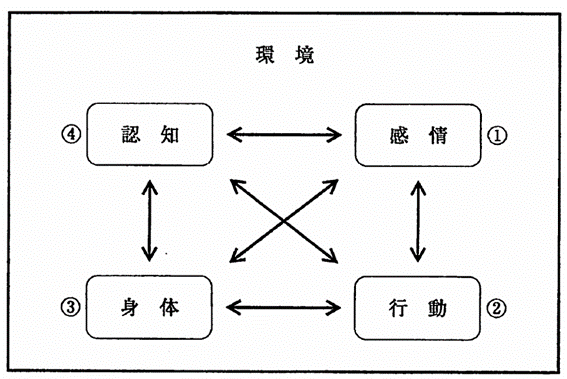

行動変容における認知行動療法の概念図を示す。この療法で問題解決法の対象はどれか。1つ選べ。

a. ①

b. ②

c. ③

d. ④

解答を見る

b